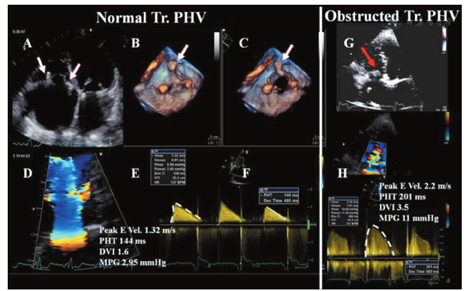

影像学方法可通过显示人工生物瓣瓣叶的退行性变(增厚、钙化、异常运动),机械性PHV缝合环的摇摆运动或阀体异常运动等证据来确定梗阻或反流的病因。机械性瓣膜的阀体应该快速并且充分地开放,在LV功能良好的情况下,其开放受限是诊断梗阻的可靠征象。在正常的双叶瓣,可能存在舒张期的轻微瓣叶震动及暂时性不对称关闭。二尖瓣开裂主要发生在后侧或外侧区域,极少发生在前侧。阀体的正常解剖学定向应当与自体瓣膜的开放极为相似,有助于保持二尖瓣流入模式及心室内LV流场,这对于LV充盈是非常重要的。对于大瓣口引导血流向前而非向后的单叶侧倾碟瓣尤为重要。人工生物瓣膜的瓣尖应很薄且动度良好,没有脱垂。对于人工主动脉瓣,观察到手术缝线、纤维蛋白条带状物或LV内气泡样回声都是正常的。瓣尖的严重钙化(图22)和阀体动度降低是瓣膜梗阻的最可靠征象。在双叶机械性瓣膜,当其中一个瓣叶的活动明显低于另一瓣叶时,可能存在明显的部分梗阻。如果不能显示阀体,当在所有切面上彩色血流图均不能充填PHV瓣口时(窄的高速前向血流束环绕混叠失真)应该怀疑存在梗阻。在人工生物瓣膜,血流束在无运动的瓣尖水平很窄,但是可以朝向支架顶端快速展开以填充瓣口。LV功能严重障碍也可引起瓣膜开放幅度降低,但这种情况将伴有彩色显像中暗淡的、低流速的血流信号。

二尖瓣PHV的多普勒超声评估(CW多普勒和PW多普勒)是通过TTE的心尖切面和TOE食管下段四腔心切面来进行的。有时需采用离轴切面来获得声束与血流束相平行的图像。

在大部分功能正常的双叶机械性PHV,其二尖瓣前向血流舒张早期峰值速率(E峰)<1.9 m/s,但在小的不匹配的人工瓣可高达2.4 m/s[90,152,153,154]。正常二尖瓣平均跨瓣压差通常<5~6 mmHg[155]。二尖瓣跨瓣血流速度和压差随狭窄程度的加重而增加。然而,人工瓣的大小、心室和心房功能、心腔的顺应性、相对的心腔压力、存在PPM或任何梗阻都可以影响跨瓣血流速度。心动过速时导致舒张期充盈时间缩短和E峰速度增加[19]。同样地,显著的二尖瓣反流引起容量负荷增加进而导致二尖瓣跨瓣血流速度增加。所有这些情况均强调了对同一患者需要进行系列随访和测量比较的必要性[14]。如果排除了上述情况,E峰速度≥2.5 m/s和二尖瓣平均跨瓣压差≥10 mmHg提示存在重度人工二尖瓣梗阻[14]。二尖瓣PHV明显梗阻的患者在负荷超声心动图时其跨瓣平均压差增加(≥12 mmHg)(图23)[36,138]。与术后即刻测量值相比发生变化时亦支持获得性PHV梗阻的诊断。在相似的心率下平均压差的增幅>5 mmHg提示存在瓣膜梗阻。

二尖瓣PHV功能正常时PHT常常<130 ms,而系列超声心动图检查PHT>200 ms则提示出现了显著狭窄。由于PHT受心率、LA和LV顺应性的影响,在心动过速或房室顺应性减低的患者,尽管存在显著人工瓣膜狭窄,其PHT仍显示为正常。在一度房室传导阻滞E峰和A峰融合时或舒张期充盈时间缩短的情况下不应测量PHT。对PHT轻度增加(130~200 ms)应谨慎解读[152,154]。

EOA和DVI(VTIPrV/VTILVOT)较少受血流的影响。EOA由连续性方程(每搏量/VTIPrV)计算得出,在合并轻度以上MR或AR时是不可靠的。在存在AR时,可用RVOT代替LVOT进行测量。相反地,由PHT推导计算的EOA在人工二尖瓣中是不适用的[106,111]。需要在排除AR的前提下对DVI进行正确解读。尽管测量值需要参照不同类型与型号的人工瓣膜的正常值,但EOA<1 cm2和DVI>2.5时须高度怀疑二尖瓣PHV存在明显梗阻[14]。

二尖瓣PHV梗阻的超声心动图评价应结合二尖瓣的2D/3D图像数据和定性、定量瓣膜梗阻程度的多普勒测量进行综合判断(图24)。必要时亦可选择其他影像学技术来评价瓣膜运动、结构和功能。例如,在无症状性人工瓣血栓形成的情况下,多普勒压差正常或仅轻度升高,需要借助荧光透视成像或心脏CT技术来识别双叶式人工二尖瓣异常的碟瓣运动[46]。数据的解读需根据瓣膜置换的时间、人工瓣的特点和血流动力学状态来进行。表15列出了评价二尖瓣PHV功能的影像学参数。当所有参数都正常时瓣膜功能异常的可能性非常低,而当大部分参数异常时PHV功能异常的可能性就很大[152]。